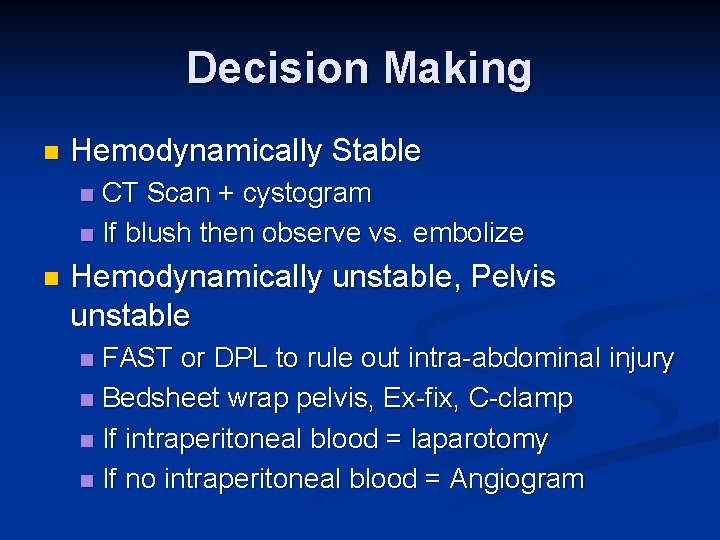

Decision Making n Hemodynamically Stable CT Scan + cystogram n If blush then observe vs. embolize n n Hemodynamically unstable, Pelvis unstable FAST or DPL to rule out intra-abdominal injury n Bedsheet wrap pelvis, Ex-fix, C-clamp n If intraperitoneal blood = laparotomy n If no intraperitoneal blood = Angiogram n